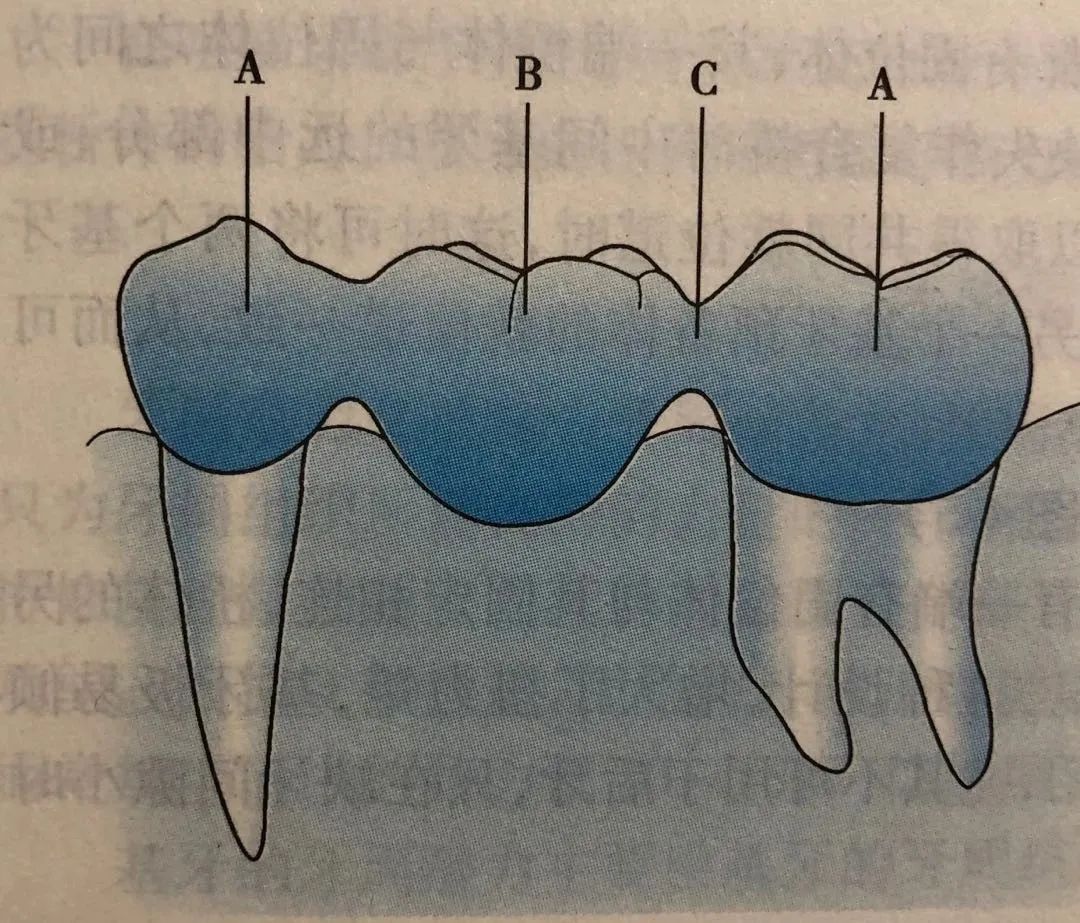

02 - 固定局部义齿

又称为固定桥,由固位体(A)和桥体(B)、连接体(C)组成。暂且可以把拔牙的地方想象成一条河,修复它就相当于建一座桥,那么桥墩就是缺失牙两侧的牙齿,套在桥墩上的部件称为固位体,桥体就是缺失牙位置的修复体。

图片来源于口腔修复学教材

为了让桥墩能够套入固位体内(A)和桥体(B)形成一个整体,我们需要对桥墩进行改造(牙体预备),部分位置倾斜的桥墩在预备前可能还需要根管治疗,然后再利用粘接剂将固定桥粘接在预备后的桥墩上。